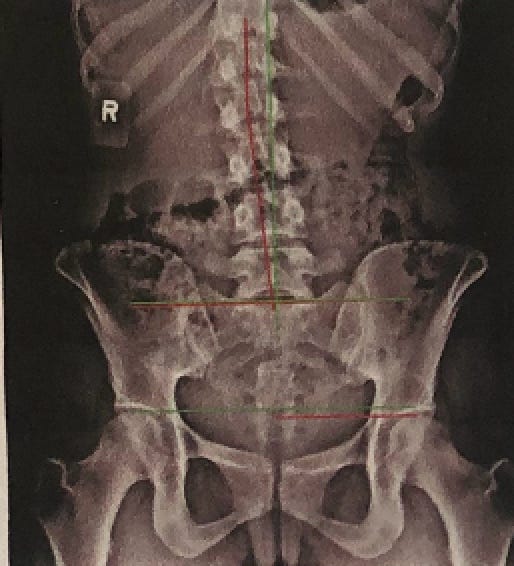

Without staying on top of my genetic imbalances, compensation can happen and happen quickly. Sometimes it’s a tight left hamstring, other times it’s been a tight left piriformis or a tight left calf. Lately it’s been a combination of all three, and it all stems from my scoliosis.

I was diagnosed with idiopathic scoliosis when I was 15 and the highest my curve ever measured was 23°—not terrible considering the degree of curvature that some of my family members have (thanks, Dutch genes! I got the scoliosis without the height.) It wasn’t enough to have me put in a brace nor be a candidate for surgery, and so I was sent to PT to complete endless clam shells.